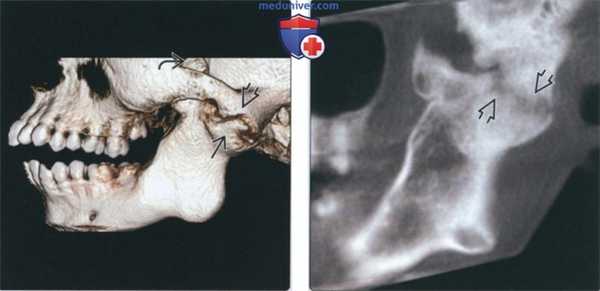

(Слева) На КЛКТ (объемный рендеринг) у подростка с пост-травматическим анкилозом определяется деформация и ремоделирование мыщелка и суставной ямки. Обратите внимание на патологически удлиненный венечный отросток (вследствие гиперплазии), расположенный выше верхнего края скуловой дуги.

(Справа) На косой сагиттальной КЛКТ левой ветви нижней челюсти определяется тонкое линейное просветление между височным и нижнечелюстным компонентом сустава, наличие которого означает фиброзное, а не костное слияние.